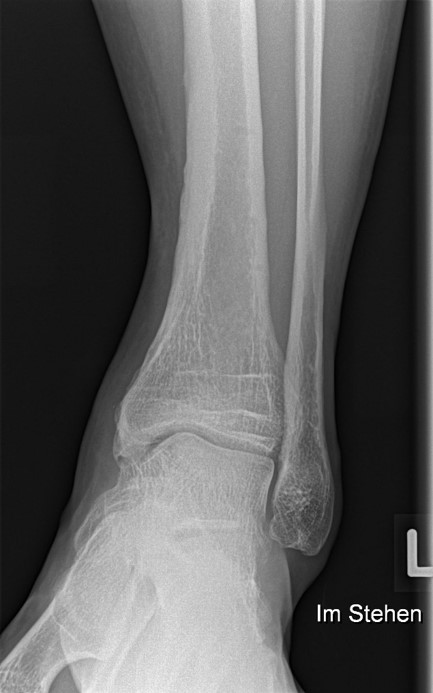

Fugengelenkfrakturen treten typischerweise vor dem 10. Lebensjahr auf, in einer Phase, in welcher die Wachstumsfugen noch weit offen sind. Dieser Frakturtyp betrifft fast ausschließlich den medialen Malleolus. Laterale Frakturen sind extrem selten, teilweise kommt es zu lateralen Bandverletzungen oder Fugenschaftfrakturen der distalen Fibula. Die Frakturlinie verläuft in einer Verlängerungslinie von der medialen Taluskante nach proximal. Häufig stellen sich Verletzungen des Innenknöchels im Röntgenbild schlechter dar, insbesondere wenn die Aufnahmen verdreht sind oder die Ebene der Fraktur bei geringer Dislokation verkippt zur Röntgenebene liegt. Besteht klinisch der geringste Hinweis auf eine Verletzung des Innenknöchels, muss aufgrund der Tragweite der Verletzung durch entsprechende Aufnahmen gegebenenfalls auch Schnittbildverfahren die Verletzung sicher diagnostiziert oder ausgeschlossen werden (Abb. 15).

„Kadiläsion“- Mediale Malleolarfraktur

Bei kindlichen Verletzungen des medialen Malleolus handelt es sich nach L. v. Laer um eine sogenannte Kadiläsion, d.h. eine Verletzung mit hohem Risiko eines schlechten Behandlungsergebnisses bei nicht korrekter Behandlung. Selbst bei optimaler Therapie ist das Risiko für spätere Wachstumsstörungen hoch, sodass diese Verletzungen nicht selten ein juristisches Nachspiel haben. Durch die Verletzung der wachstumsaktiven Zone kann es zu einem vorzeitigen Verschluss der Wachstumsfuge kommen, mit entsprechendem Fehlwachstum. Das Risiko eines vorzeitigen Verschlusses der Wachstumsfuge korreliert mit dem Ausmaß der Schädigung der wachstumsaktiven Zone. Ab dem 13. Lebensjahr wird das Risiko bei reduzierter Wachstumsaktivität zunehmend geringer.

Fugengelenkfrakturen können die Wachstumsfuge durchkreuzen (Abbildung 16a), ohne oder nur mit minimaler Beteiligung der Fuge sehr weit medial liegen (Abbildung 16b) oder durch die Fuge auslaufen (Abbildung 16c). Relevant für die Wachstumsprognose ist weniger die Form der Fraktur, sondern das Alter des Patienten zum Zeitpunkt des Traumas sowie das Ausmaß der Schädigung der Wachstumsfuge, wobei eine Korrelation mit dem Ausmaß der Dislokation besteht.